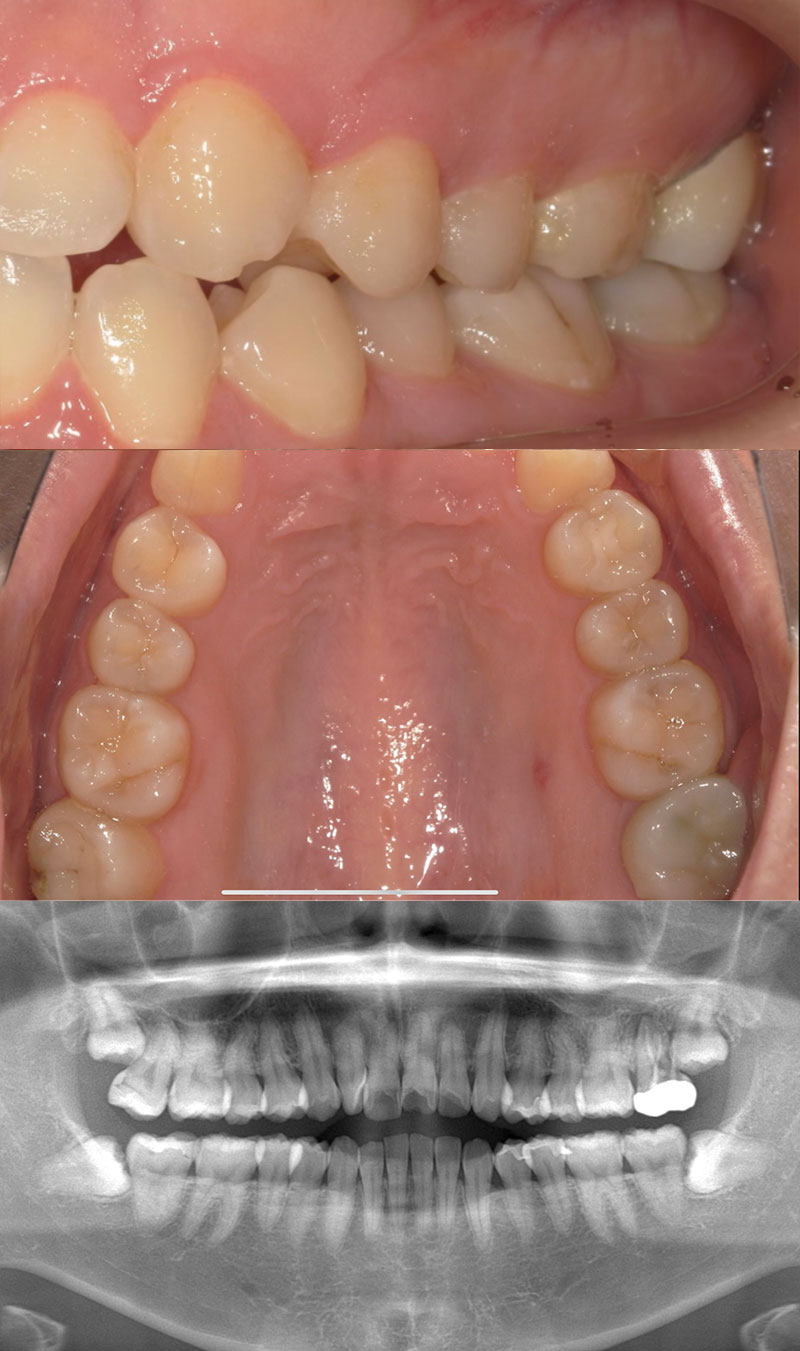

患者さんの悩みは抜歯した歯の部分を矯正で治したいのと、八重歯が気になること、上の歯の正中(真ん中)が合っていないことでした。

マウスピース矯正希望とのことだったので、アンカースクリューを用いてしっかりした固定を得て、空いたスペースに歯を動かすことをご提案いたしました。

患者さんの悩みであった前歯の見た目としっかりスペースを閉じ噛み合わせが改善されてとても喜ばれていました。

| 患者様 | 30代男性 |

| 主訴 | 上下前歯の重なりが気になる |

| 所見 | 右上第一小臼歯が欠損しているため、スペースを利用して犬歯・第一小臼歯、を遠心に移動する必要あり |

| 治療装置 | インビザライン、アンカースクリュー |

| 装置装着部位 | 全顎 |

| 治療費 | 矯正費88万円(税込) アンカースクリュー埋入費:33,000円(税込) |

| 治療期間 | 約2年4か月(約30回通院) |